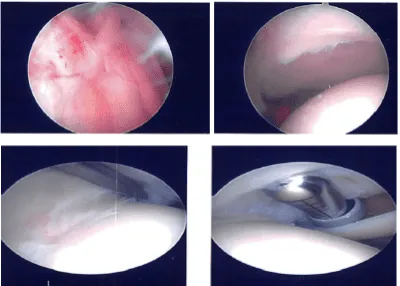

Entry portal was made laterally with a lateral parapatellar incision. Arthroscope was entered. Patellofemoral joint showed no injury. A medial plica could be seen. The scope was entered in the medial tibiofemoral compartment. Medial entry portal was made with the use of a spinal needle.

The medial compartment showed no tear of the medial meniscus. There was no cartilage tear. The scope was entered into an intercondylar notch. The ACL was intact with subtle degeneration.

The scope was entered into the lateral compartment where there was some fraying of the medial margin of lateral meniscus which was cleaned with the use of shaver and biter. No other meniscal tear was found.

Scope was entered into the patellofemoral compartment where there was no cartilage damage though there was patellar maltracking. There was a medial synovial plica which was prominent. It was debrided with the use of a shaver.

Final pictures were taken and saved. The knee was irrigated and drained. Knee was closed with nylon # 3-0. Naropin 9 cc mixed with 40 mg of Depo-Medrol was injected into the knee.

Intraoperative Arthroscopy Images